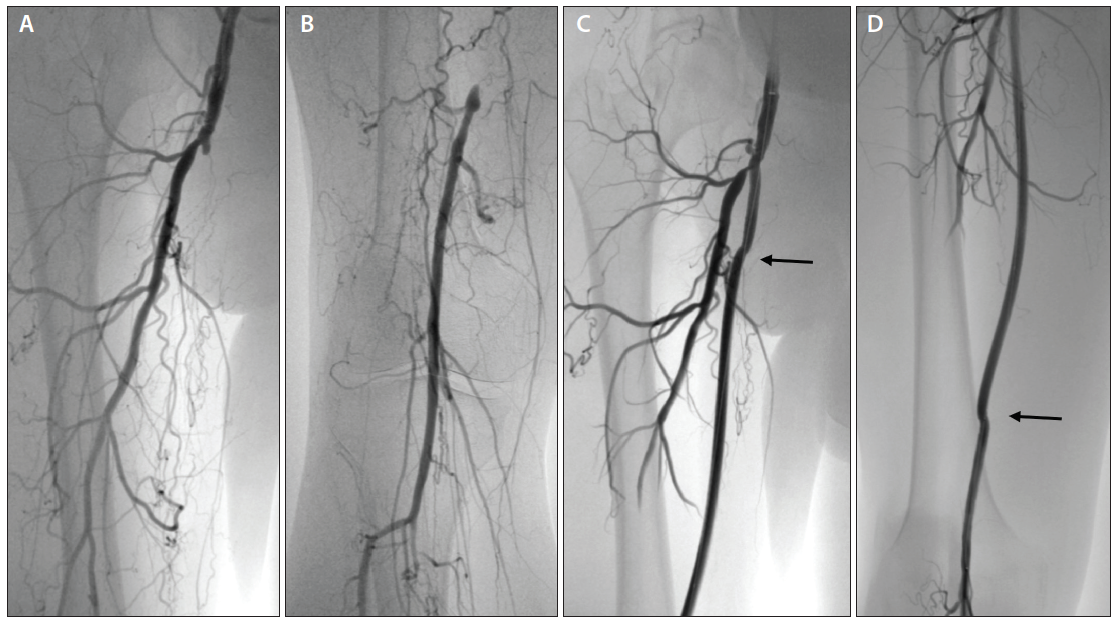

CFA, Profunda, and SFA Disease Vascular Disease Management What Is Sfa Disease Occlusive peripheral arterial disease is blockage or narrowing of an artery in the legs (or rarely the arms), usually due to atherosclerosis and resulting in decreased blood flow. Evaluating the value of drug delivery and the role of permanent implants in treating superficial femoral artery disease. Focussing on the superficial and popliteal artery, there are currently several clinical trials under. What Is Sfa Disease.